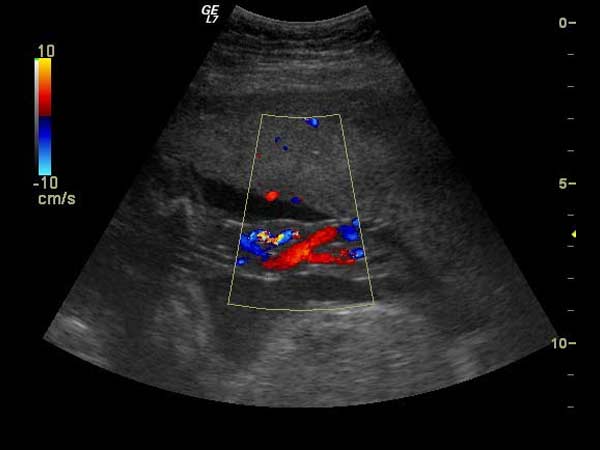

Om te weten of een paard voldoende in conditie is voor de gevraagde prestaties, voert EquiSound melkzuurbepalingen uit. Ook inspanningstesten met Holter monitoring om de hartfrequentie te controleren wanneer het paard werkt behoren tot de mogelijkheid. Op basis van deze onderzoeken kan het trainingsschema geoptimaliseerd worden. Echocardiografie met Doppler is aangewezen indien er tekenen zijn die op hartziekten wijzen en die verder onderzocht moeten worden.